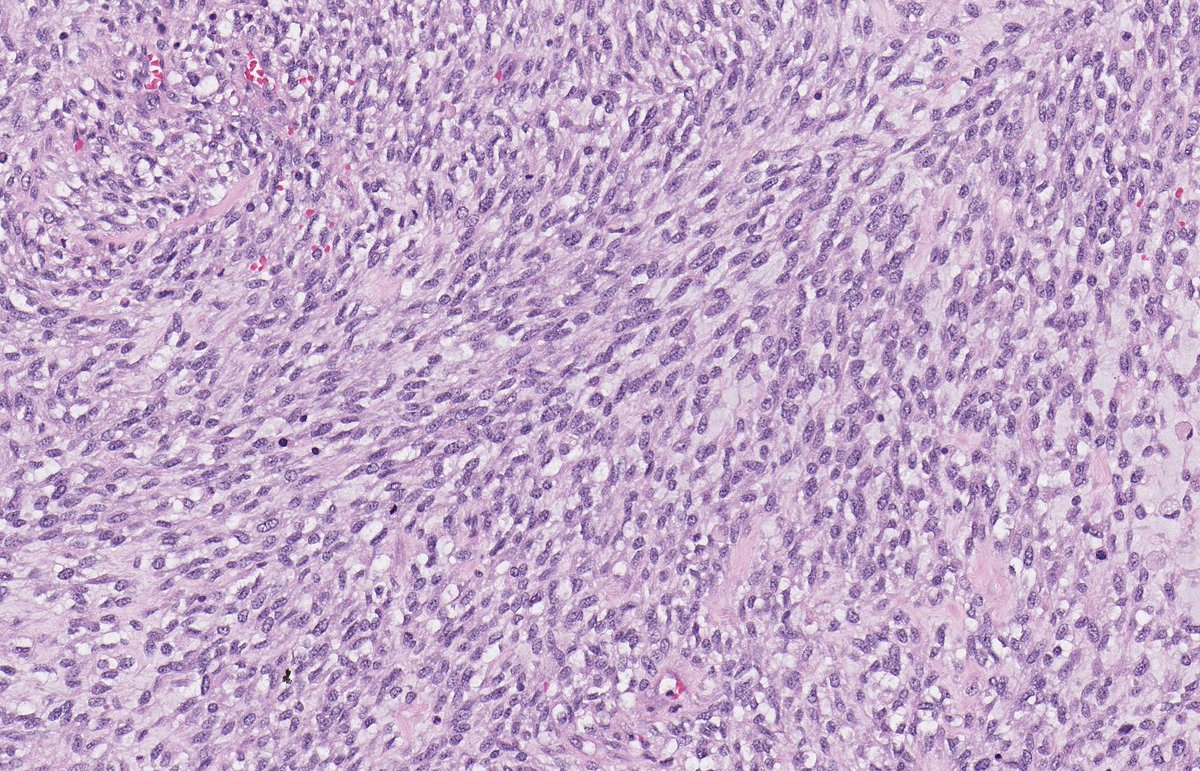

MALIGNANT PERIPHERAL NERVE SHEATH TUMOUR. Underlying NF1. IHC: SOX10, H3k27me3. NB: spindle-epithelioid cells with pale amphophilic cytoplasm; ovoid-round nuclei with moderate pleomorphism and conspicuous mitotic activity; variable collagenous-myxoid stroma.